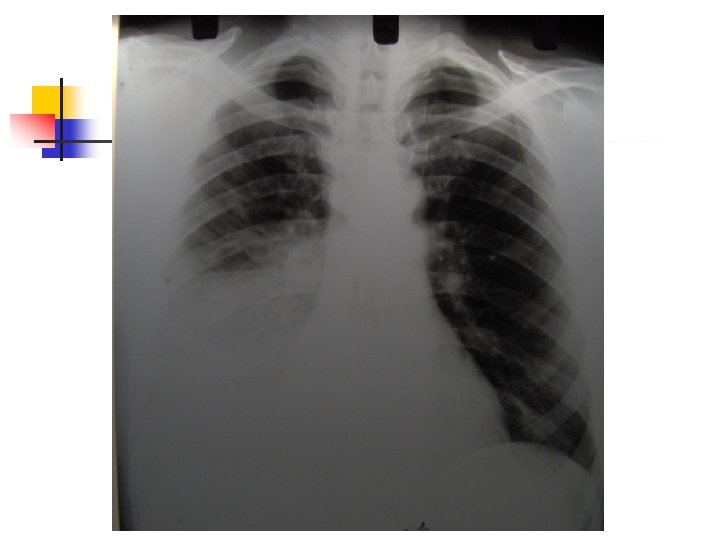

Aproximación diagnóstica: Radiología n n n 250 ml son necesarios para provocar alteraciones radiológicas. Primer signo: Borramiento del SCD Damoisseau. Desviación de estructuras. Derrame tabicado.